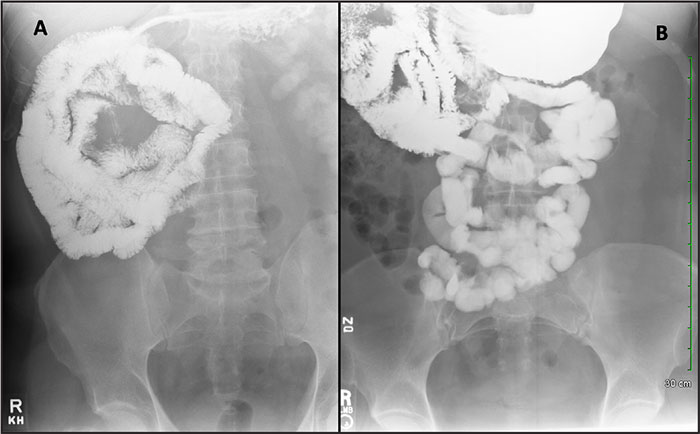

α) Διάβαση λεπτού εντέρου: Είναι, η συνήθης εξέταση του στομάχου του λεπτού εντέρου και γίνεται με χορήγηση βαρίου αραιάς πυκνότητας. Χορηγείται, όμως μεγάλη ποσότητα, ώστε να επιτυγχάνεται ικανοποιητική πλήρωση του λεπτού εντέρου αφ΄ενός και ταχεία κένωση του στομάχου αφετέρου. Η παρατεταμένη παραμονή του βαρίου στο λεπτό έντερο, ακόμη και σε φυσιολογικά άτομα, προκαλεί κροκύδωση και διάσπαση της στήλης του σκιαγραφικού υλικού και ως εκ τούτου ανεπαρκή απεικόνιση των πτυχών του εντέρου. Εκτελείται έπειτα από την κατάποση κάψουλας βαρίου και παρακολουθείται ακτινοσκοπικά. Η εξέταση αυτή βοηθά στην αναγνώριση και τον προσδιορισμό της έκτασης προσβολής του λεπτού εντέρου, της ύπαρξης πιθανών επιπλοκών (στενώσεις, συρίγγια), ανάδειξη όγκων και προηγούμενων χειρουργικών εκτομών και παρακάμψεων. Ο εξεταζόμενος πρέπει τρεις ημέρες πριν την εξέταση να αρχίσει δίαιτα χωρίς υπόλειμμα, δηλαδή να τρώει κρέας, ψάρι ή κοτόπουλο, τα οποία συνοδεύονται με ζωμούς. Απαγορεύονται αυστηρώς τα χορταρικά, το ψωμί, τα όσπρια, τα φρούτα και ότι περιέχει ίνες. Την ημέρα της εξέτασης πρέπει ο εξεταζόμενος να είναι νηστικός, καθώς και να μην πίνει υγρά.

β) Εντερόκλυση: Εισάγεται σκιαγραφική ουσία κατευθείαν στο λεπτό έντερο με τη βοήθεια καθετήρα. Η μέθοδος υπερέχει των άλλων δύο εξετάσεων, γιατί η πλήρωση του λεπτού εντέρου δεν εξαρτάται από την κένωση του στομάχου, η ταχύτητα διέλευσης του βαρίου από τις έλικες επηρεάζεται από την ταχύτητα χορηγήσεως και επιτυγχάνεται ικανοποιητική διάταση του εντέρου.